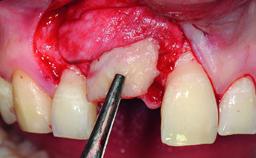

Replacement of an Ankylosed Upper Left Central Incisor: Bone Augmentation and Socket Grafting, Late Placement of an RC Bone Level Implant

A 15-year-old male patient was referred to us by his pediatric dentist in June 2004 for evaluation of treatment options for his failing tooth 21. The patient had recently seen an endodontist for internal bleaching and been advised that there had been significant resorption and ankylosis. The patient’s mother was concerned because the tooth appeared shorter than the adjacent one. His past dental history was significant for trauma (September 2001), where the tooth had been avulsed and reimplanted. Teeth 11 and 21 had been endodontically treated.